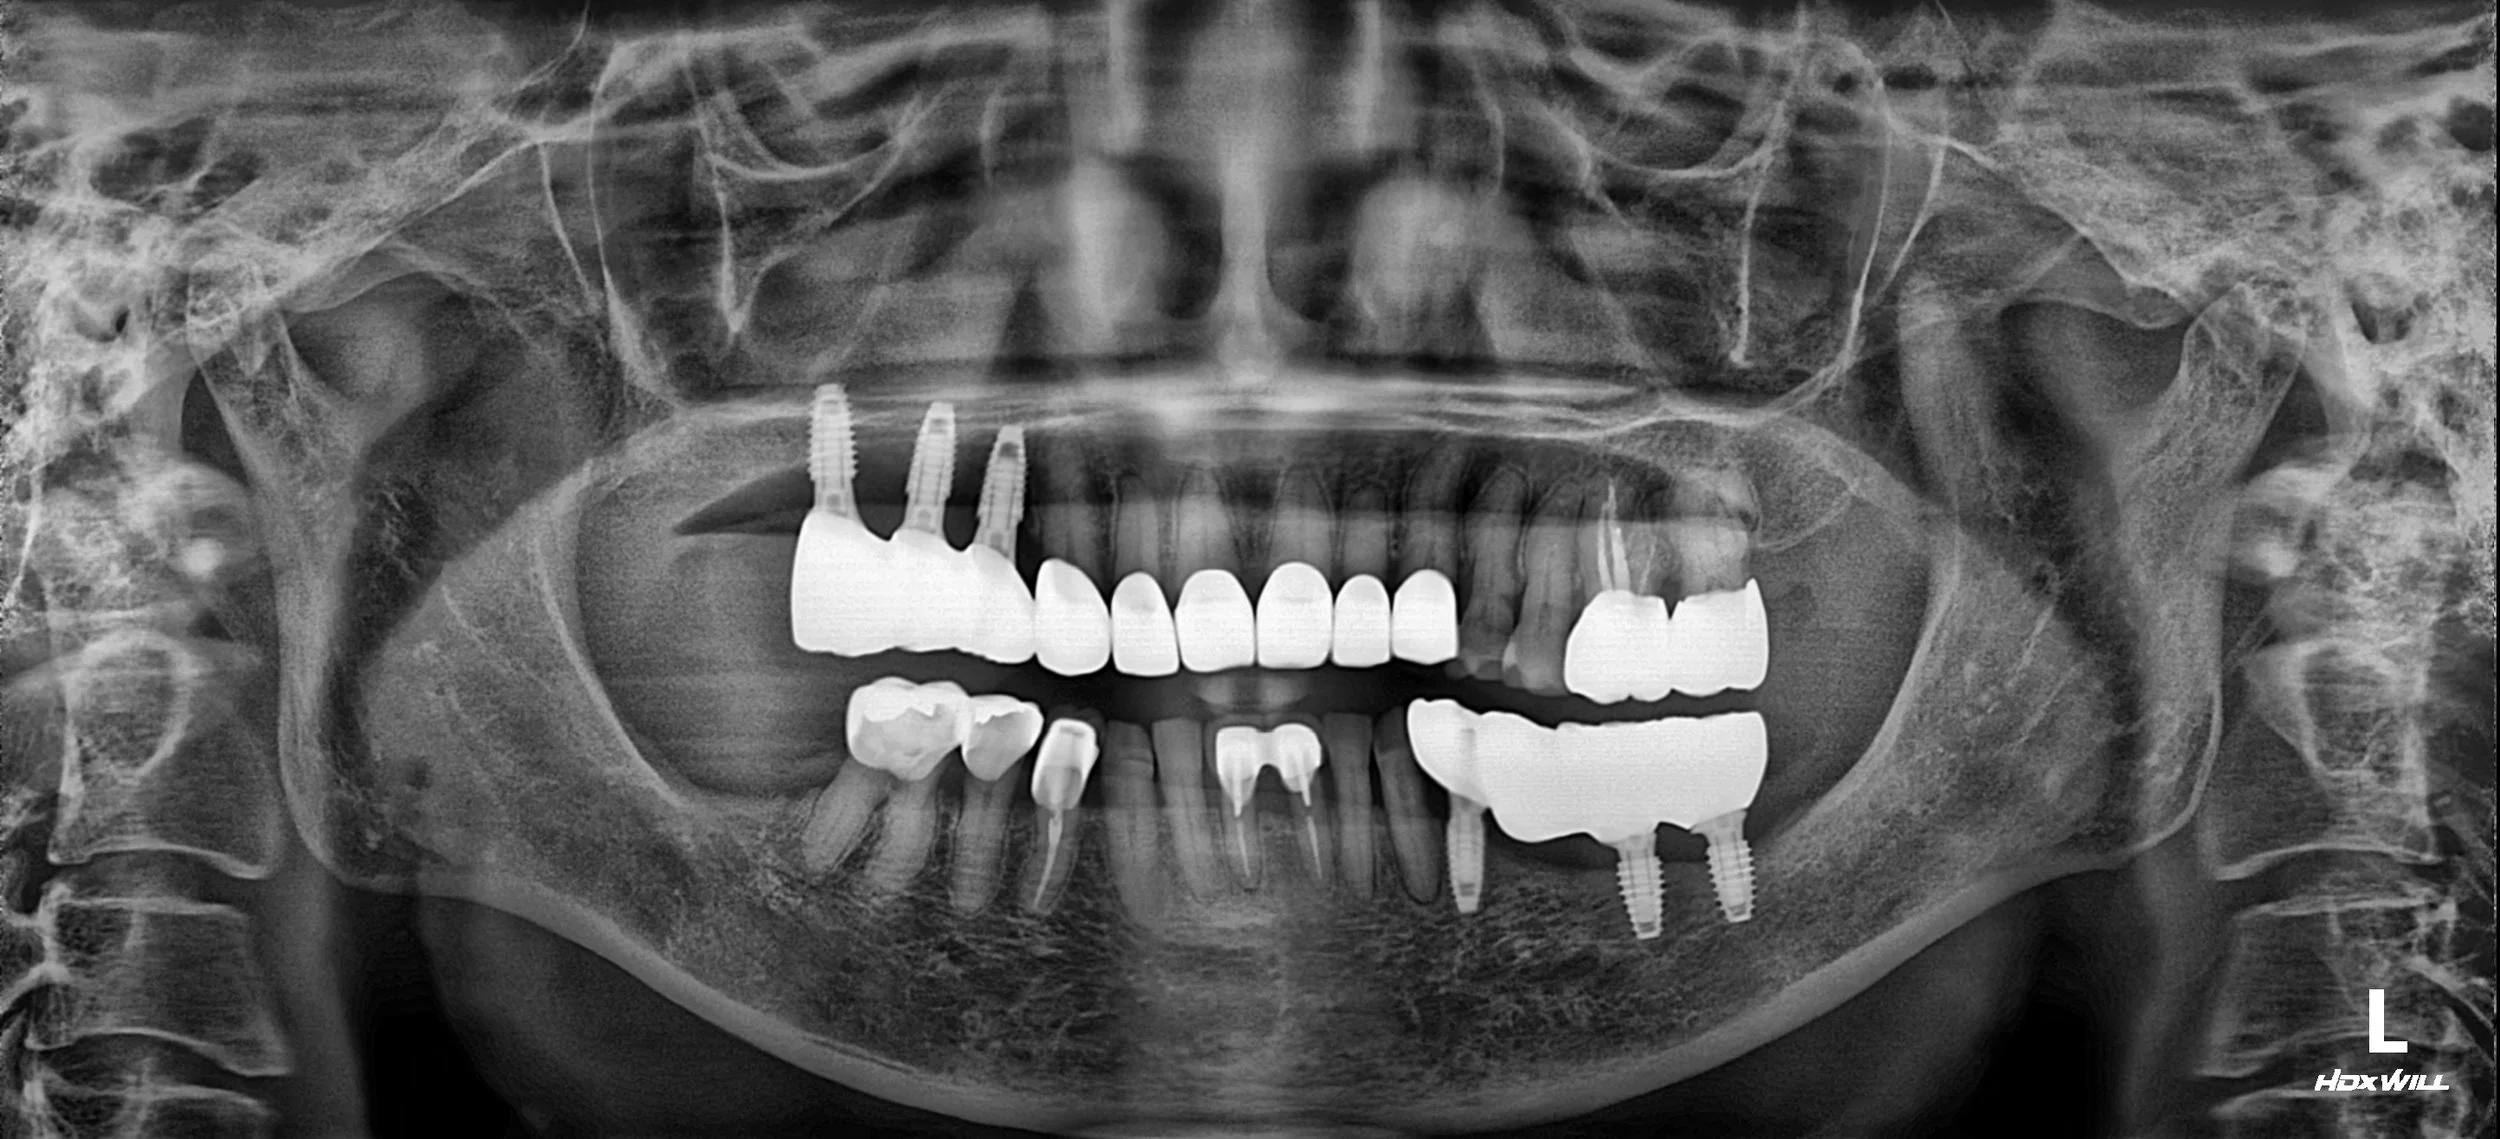

Posterior implant-supported restorations were placed to re-establish posterior support,

followed by anterior prosthetic rehabilitation to correct the crossbite relationship.

Due to the Class III skeletal tendency, excessive overbite correction was avoided.

Certain teeth (e.g. #33) were intentionally excluded from occlusal contact to reduce anterior overload.

A prolonged period of occlusal adjustment and mandibular adaptation exercises was undertaken

before finalising the definitive prostheses.

The case was completed with an edge-to-edge anterior relationship to minimise the risk of prosthetic fracture

while maintaining functional and aesthetic balance